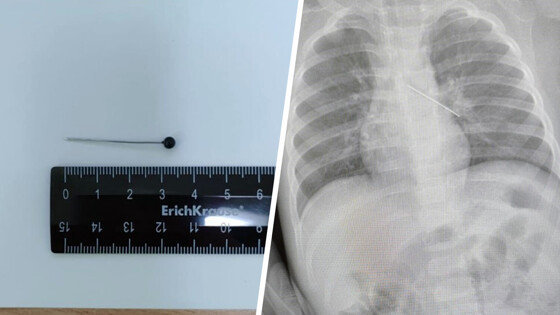

Врачи Центра охраны материнства и детства спасли 17-месячного ребенка, который из любопытства проглотил булавку. Об этом сообщила президент медицинского учреждения Лариса Белоцерковцева в Telegram-канале.

По словам медика, мать мальчика вовремя заметила беду и привезла ребенка в медицинское учреждение. Обследование показало, что инородный предмет зафиксировался в бронхах.

«Если бы бригада наших высокопрофессиональных специалистов не смогла удалить инородный предмет с помощью бронхоскопа, ребенка пришлось бы передавать торакальным хирургам для проведения большой операции», — пояснила Белоцерковцева.